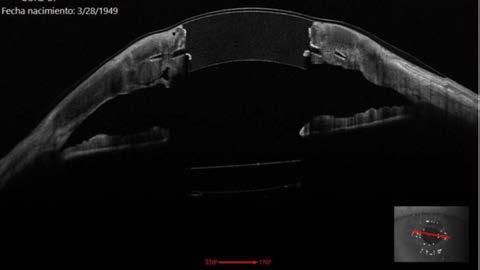

La técnica de implantación es modificada de la técnica usada en conejos y utiliza anestesia general y un tomógrafo de coherencia óptica (OCT) intraoperatorio. Se sutura un anillo de Flieringa y se trepana parcialmente una porción de 4 a una profundidad aproximada de dos tercios del grosor corneal. Se realiza un bolsillo intraestromal de 360° usando una cucharilla angulada de doble bisel. Es importante dejar un grosor de una lamela anterior entre 200 a 400 micras. Se realiza una paracentesis y se ingresa viscoelástico a cámara anterior. Se realiza una escisión del botón corneal con diámetro de 4 mm usando tijeras tras profundizar la trepanación inicial. El dispositivo de Gore es introducido con un fórceps y rotado usando un Sinskey. Esto permite maniobrar la falda flexible del dispositivo hasta estar 360° dentro del bolsillo estromal sin doblar. Se confirma la posición del dispositivo mediante el uso de OCT intraoperatorio. Se sutura el dispositivo con 16 suturas interrumpidas de nylon 10-0 del tejido corneal receptor al centro del dispositivo para evitar retracción del centro óptico. Se irriga la cámara anterior con solución salina balanceada para eliminar el viscoelástico y evitar picos hipertensivos.

Figura 1. Fotografía en lámpara de hendidura de un dispositivo sintético corneal de Gore. Un mes después de su implante.

Figura 2. OCT de segmento anterior dispositivo sintético corneal de Gore. Un año después de su implante.